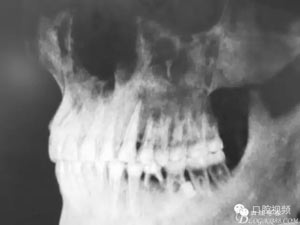

圖1.術(shù)前的全景片影像檢查,35移位至36、37之間。